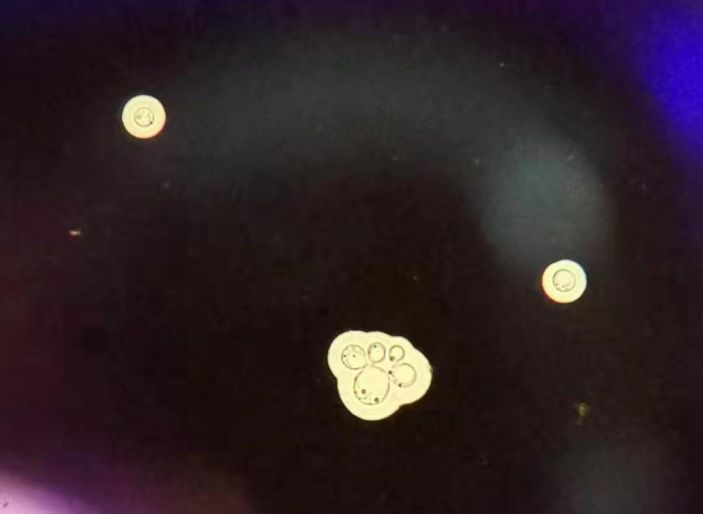

△檢驗科實驗室腦脊液培養出來的隐球菌(顯微鏡下)。